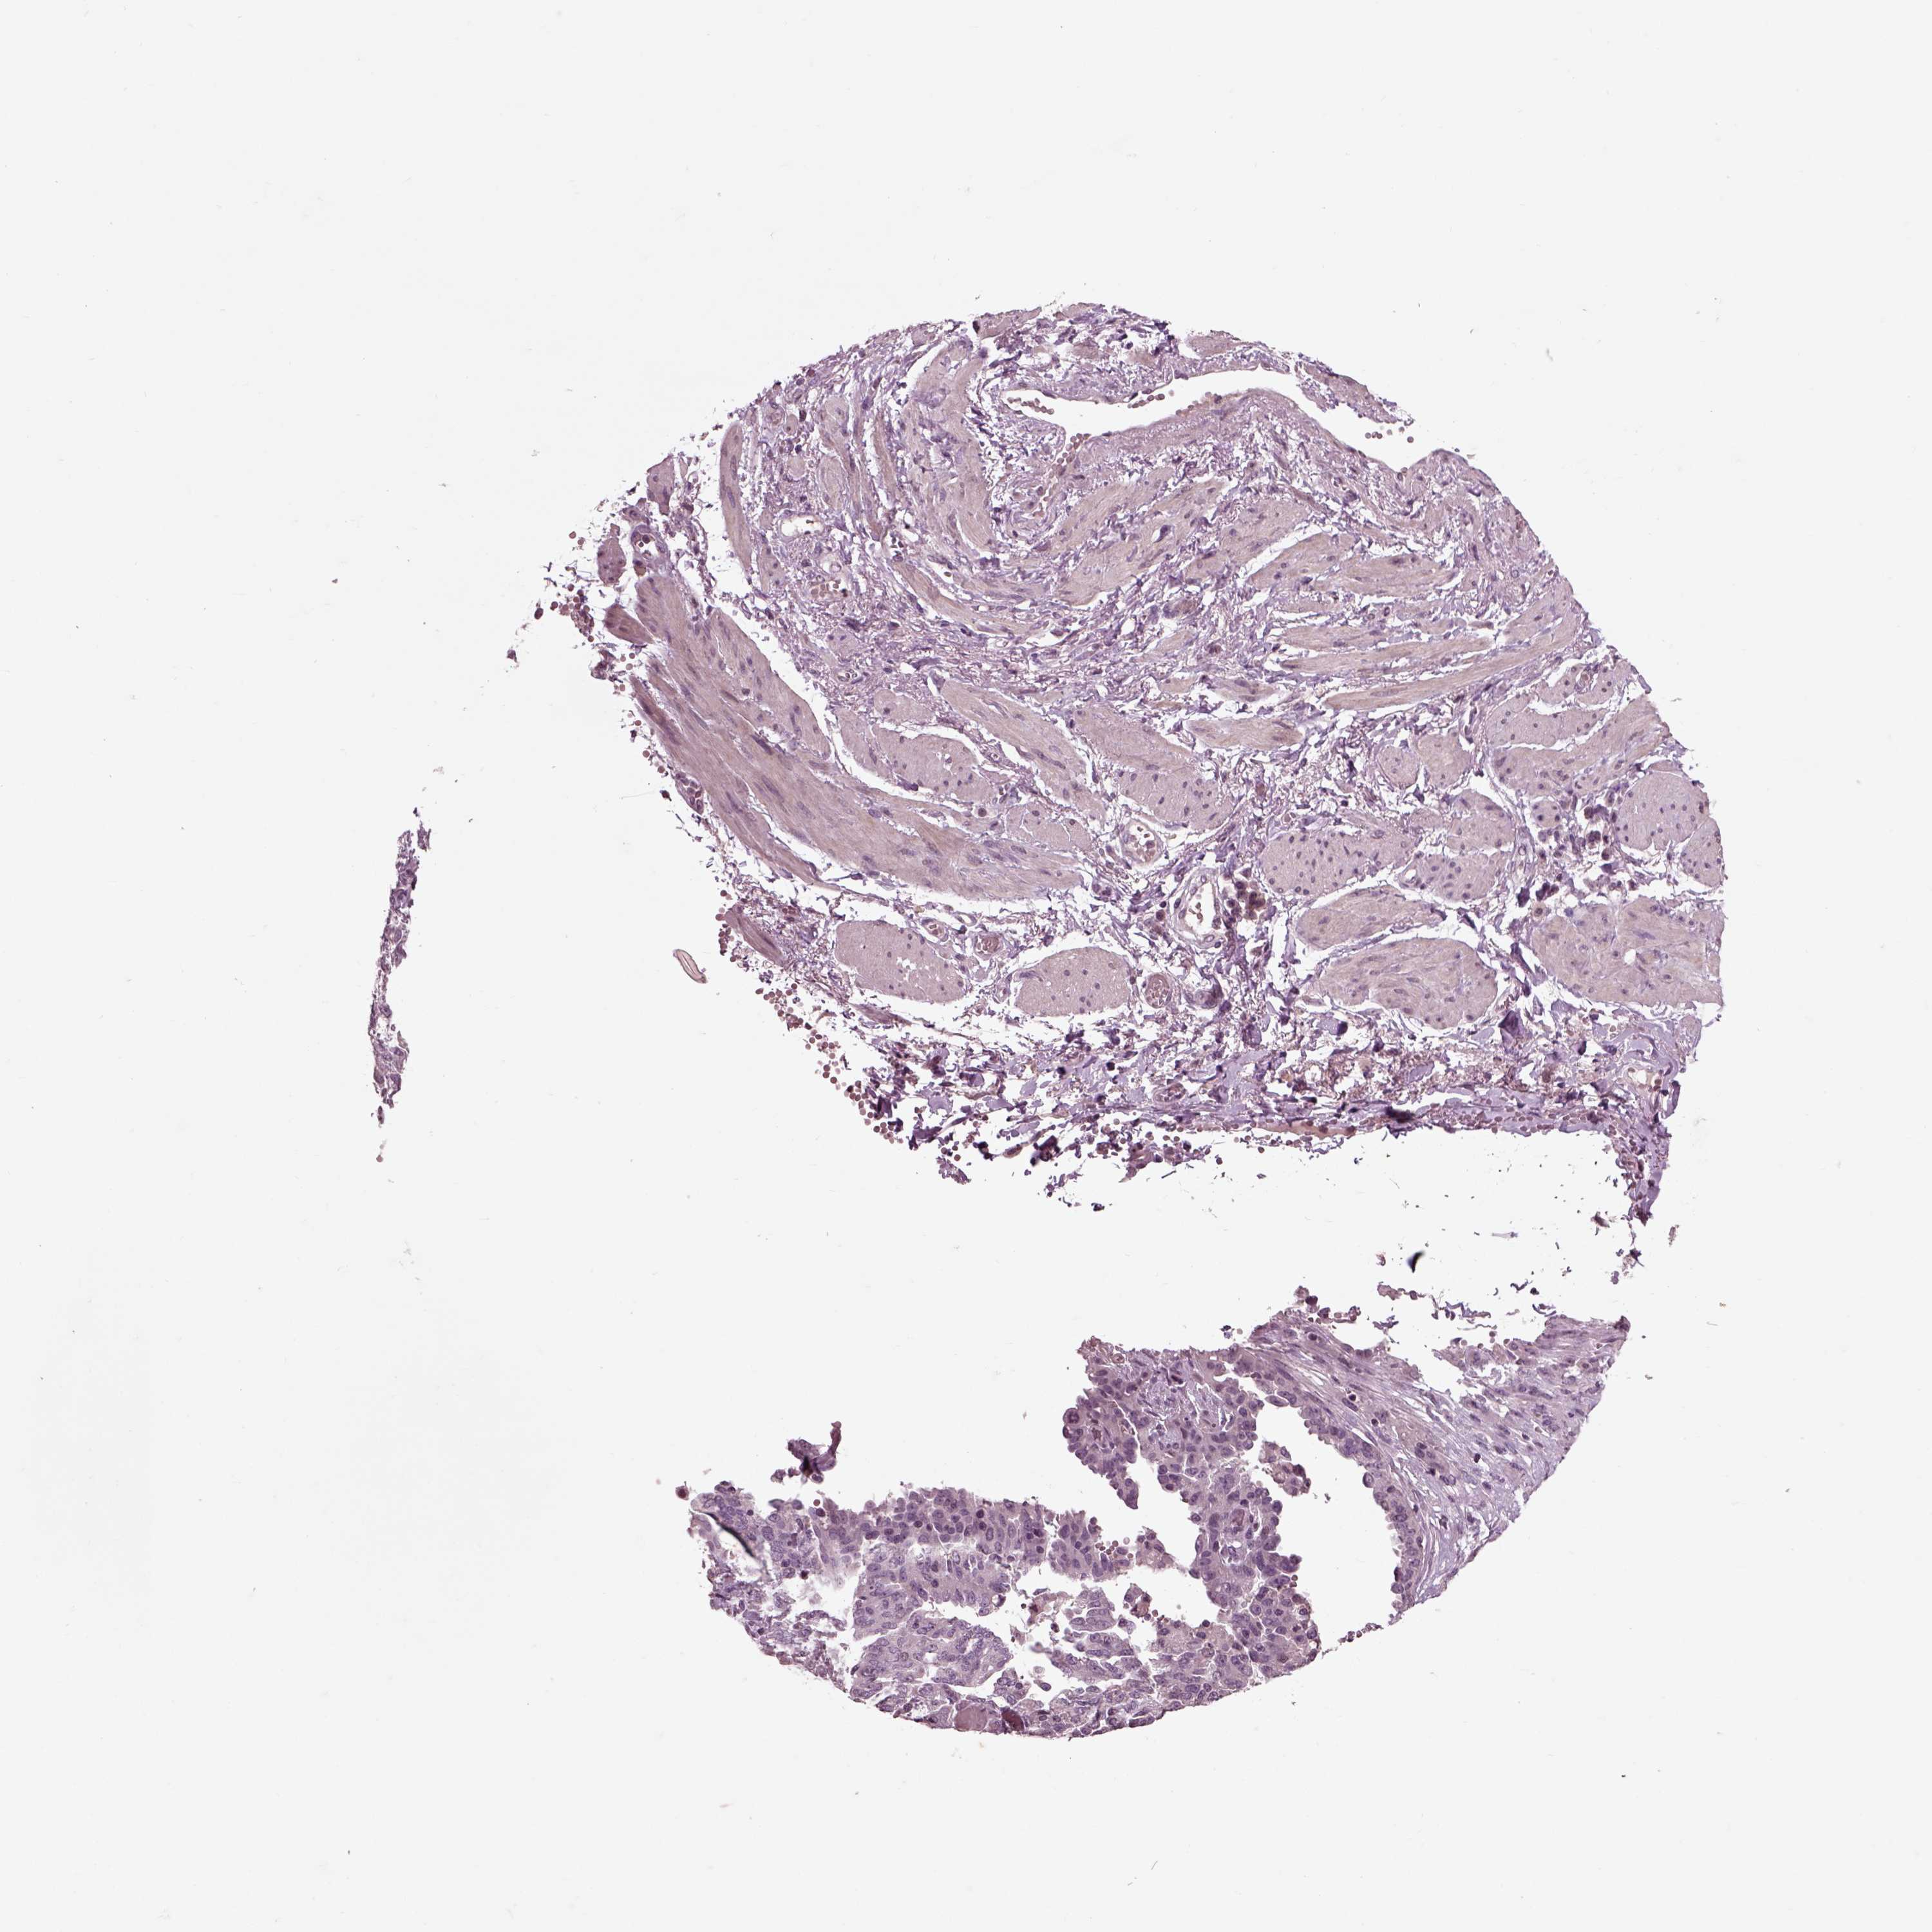

OVARIAN CANCER - Protein expressioni

A mouse-over function shows sample information and annotation data. Click on an image to view it in a full screen mode. Samples can be filtered based on level of antibody staining by selecting one or several of the following categories: high, medium, low and not detected. The assay and annotation is described here.

Note that samples used for immunohistochemistry by the Human Protein Atlas do not correspond to samples in the TCGA dataset.

Antibody stainingi

Antibody staining in the annotated cell types in the current human tissue is reported as not detected, low, medium, or high, based on conventional immunohistochemistry profiling in selected tissues. This score is based on the combination of the staining intensity and fraction of stained cells.

Each image is clickable and will lead to virtual microscopy that enables deeper exploration of all samples and also displays staining intensity scores, fraction scores and subcellular localization as well as patient and tissue information for each sample.

Antibody HPA008759

Antibody HPA012602

Antibody CAB009403

Cystadenocarcinoma, serous, NOS

Cystadenocarcinoma, mucinous, NOS

Carcinoma, endometroid